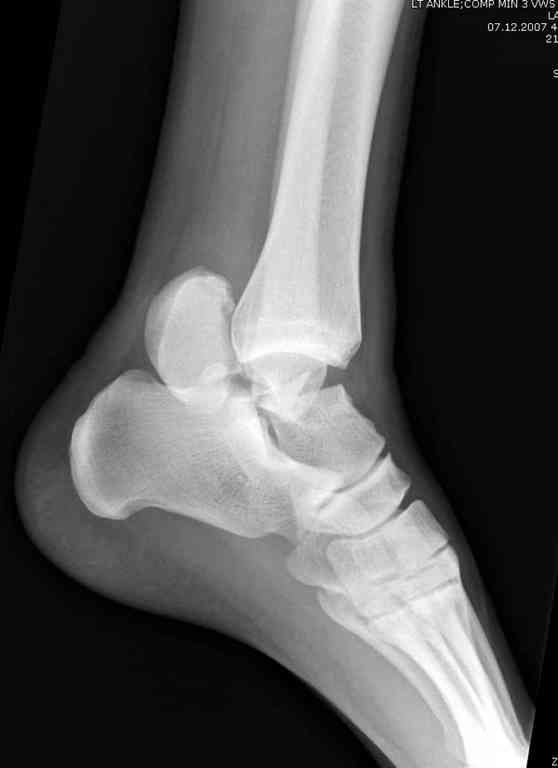

Из-за многооскольчатости дистальной части малоберцовой, где невозможно было провести фиксацию шурупами, перелом зафиксирован подпирающей пластиной, которая должна служить дополнением отсутствующей дистальной части малоберцовой (lateral cortex substitute).

Для стабильности два шурупа на синдесмоз.

Медиальную рану с приближенными краями продолжаем вакуумировать (KCI). Наружный фиксатор оставлен на пару недель, надеюсь, небольшая рана будет гранулировать и закроется без кожной пластики. Фиксация медиальной ложыжки не планируется.